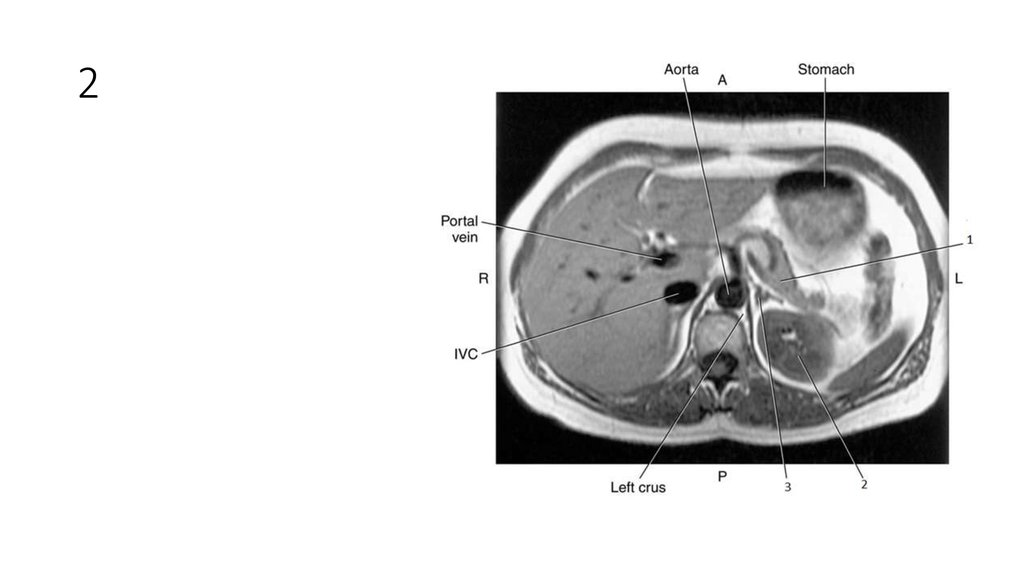

46. 2

47. 2

• Left Kidney

48. 3

49. 3

• Left Adrenal Gland